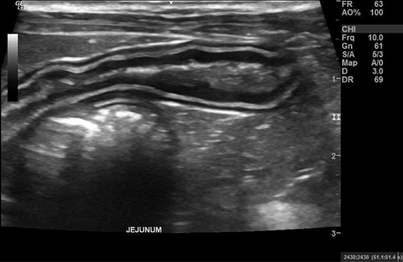

Just like in human medicine, veterinary ultrasound is just as important and beneficial. Ultrasound can aid in diagnosing many cases in which x-rays and bloodwork alone cannot.

Ultrasound can greatly increase diagnostic efficiency in your practice translating into better care for your patients.